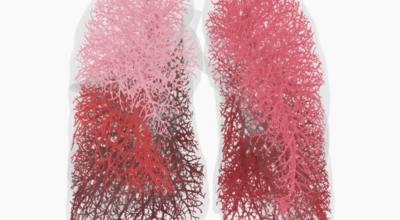

건강한 폐를 위해서는 폐의 활동을 유지하는데 도움을 주는 건강에 좋은 음식을 섭취해야 합니다. 폐는 우리 몸에서 중요한 역할을 하는 것은 말할 필요도 없어요. 그러나 결국 폐는 공기 뿐만 아니라 대기 오염과 담배 연기 같은 유해한 요소를 흡입하게 되는데요. 이런 오염 물질은 천식, 기관지염, 낭포성 섬유증 또는 폐렴등의 호흡기 건강 문제의 위험을 증가시켜요.

세계보건기구인 WHO 에 의하면 2억 3천5백만 명이 천식으로 고통 받고 있으며 이는 진단 또는 치료가 부족한 상태이지요. 그렇기 때문에 폐 건강을 향상시키기 위해서는 폐에 좋은 음식을 섭취할 필요가 있어요.